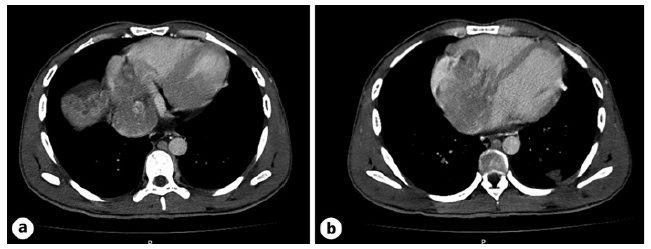

A 25-year-old male patient from Guinea, in Portugal for 6 months, with no known medical history presented with a 2-week history of fatigue, exertional dyspnea, anorexia, and weight loss. He also mentioned abdominal pain for the last 4 days. The patient consumed 20 g of alcohol per week and had no history of drug consumption or tobacco smoking habits. He was employed as a construction worker and did not have any relevant travel history. Physical examination showed a systolic murmur in the tricuspid area, an enlarged liver and right upper quadrant pain, with no ascites or signs of chronic liver disease stigmata. The electrocardiogram revealed sinus tachycardia with a right bundle branch block and the chest radiograph showed an enlarged cardiac silhouette. An echocardiogram showed an intracardial mass in the right atrium (RA) (80 mm × 64 mm), obstructing the tricuspid valve and causing functional stenosis. His laboratory tests showed normocytic anemia (hemoglobin 11.6 g/dL [ref. 13-17.5]), slightly elevated liver enzymes (AST 91 U/L [ref. 0-34], ALT 68 U/L [ref. 10-49], GGT 68 U/L [ref. 0-60], ALP 393 U/L [ref. 35-105]), with normal bilirubin (1.12 mg/dL [ref. <1.2]), and elevated NT-proBNP (457 pg/mL [ref. <300]). He underwent a computed tomography scan of the thorax, abdomen, and pelvis, which revealed multiple coalescent lesions evolving mainly the left and caudate lobes, consistent with multicentric HCC (shown in Fig. 1). Additionally, macrovascular invasion was observed in the left portal vein, middle suprahepatic veins, and inferior vena cava, extending into the lumen of the right ventricle and atrium. The intracardiac component measured 9 × 7.5 × 6 mm (AP ×T×L)(shown in Fig. 2). The computed tomography scan also identified bilateral pulmonary secondary lesions and signs of multiple segmental and sub-segmental bilateral pulmonary embolisms. Fur-ther investigation revealed an HBV infection (AgHbs positive, anti-Hbs negative, AgHbe positive, anti-Hbe negative) with a viral load of 1,160,000 IU/mL and an alpha-fetoprotein of 357,440 ng/mL (ref. <7). The patient was classified as Barcelona Clinic Liver Cancer (BCLC) Stage C due to the presence of extra-hepatic spread and portal invasion.

Fig. 1. CT scan of the abdomen. Heterogeneous hepatomegaly with multiple coalescent lesions involving most of the left and caudate lobes and also the right lobe, with arterial enhancement and washout, suggestive of multicentric HCC. CT, computed tomography.